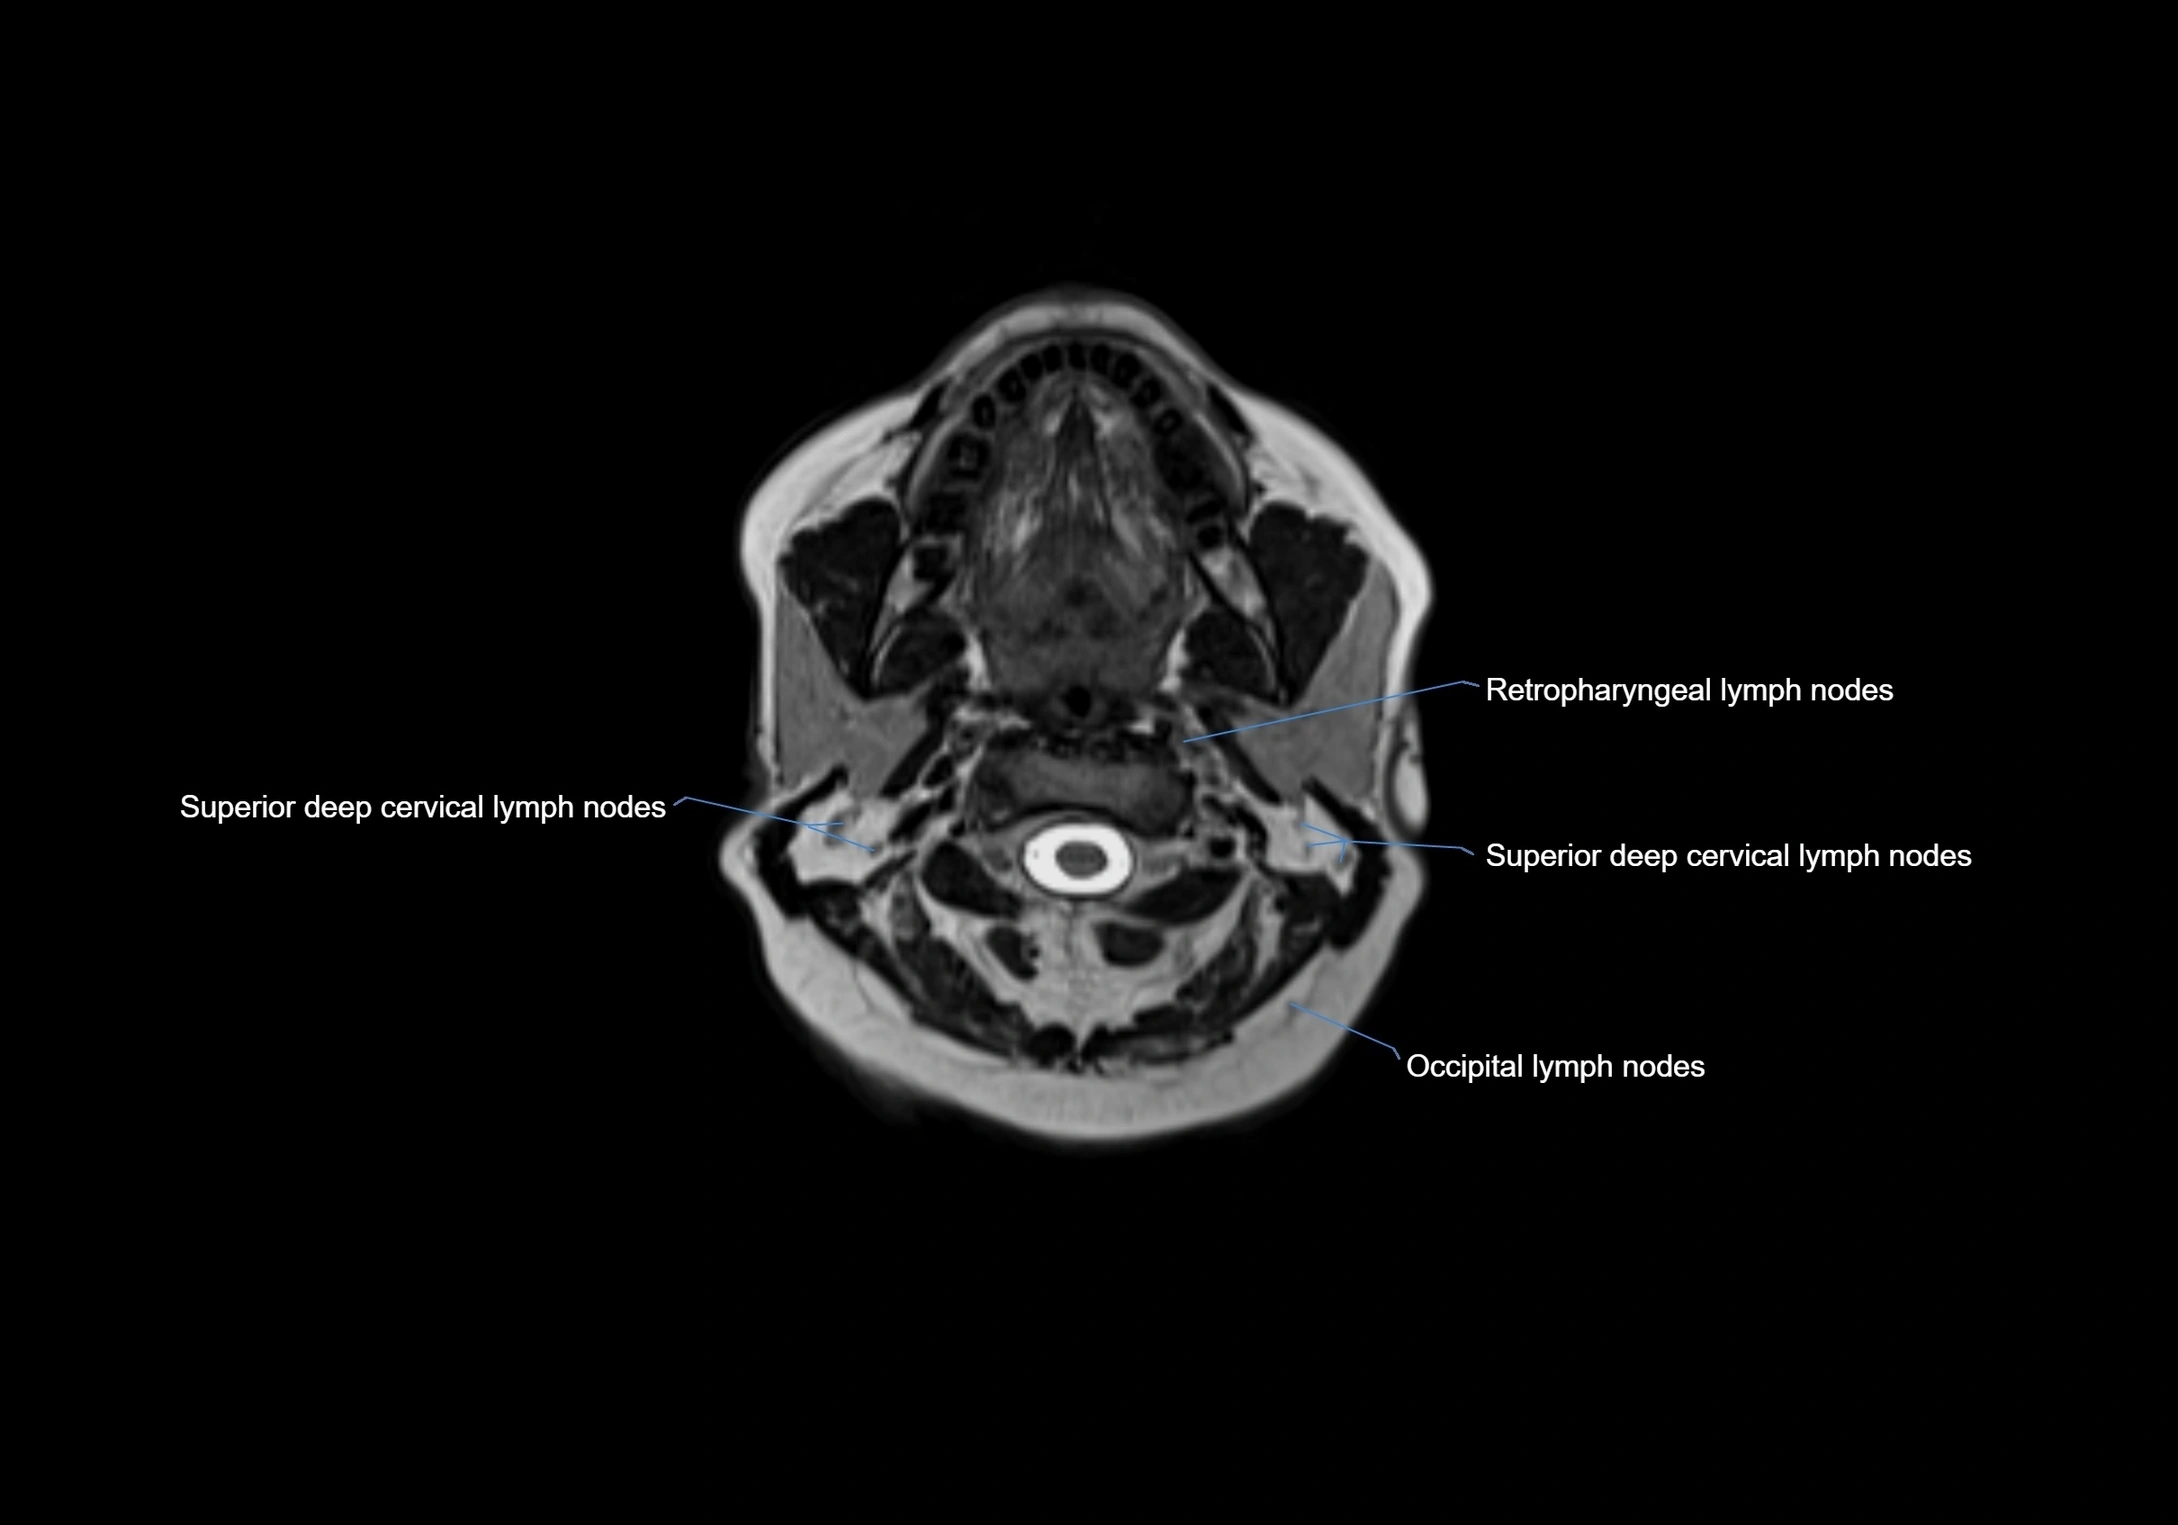

MRI Appearance

T1-weighted images:

• Normal accessory nodes appear as small, oval hypointense to intermediate signal structures within subcutaneous fat

• Surrounded by hyperintense fat, enhancing contrast for visualization

• Pathological nodes may appear enlarged or rounded, sometimes with cortical thickening

MRI images

image